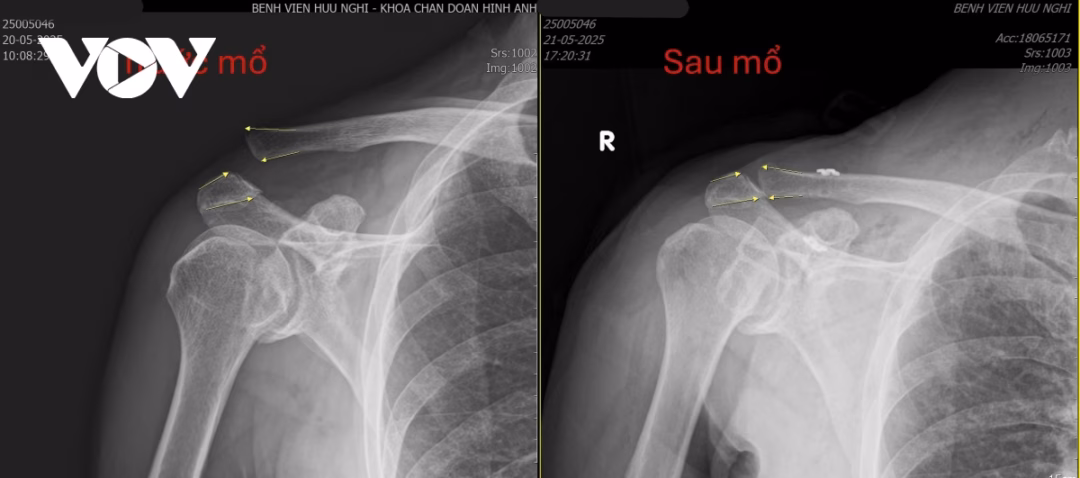

Sau khi đến khám tại Bệnh viện Hữu Nghị, qua thăm khám lâm sàng và chụp X-quang, MRI, các bác sĩ đã chẩn đoán ông bị trật khớp cùng – đòn kèm theo đứt dây chằng quạ – đòn. Sau hội chẩn chuyên môn, bệnh nhân được chỉ định phẫu thuật đặt lại khớp và tái tạo dây chằng quạ – đòn bằng kỹ thuật hiện đại.

Ca phẫu thuật được thực hiện an toàn, không biến chứng và đạt kết quả tốt. Bệnh nhân được theo dõi và chăm sóc tích cực sau phẫu thuật, giúp ông sớm phục hồi và trở lại sinh hoạt hàng ngày.